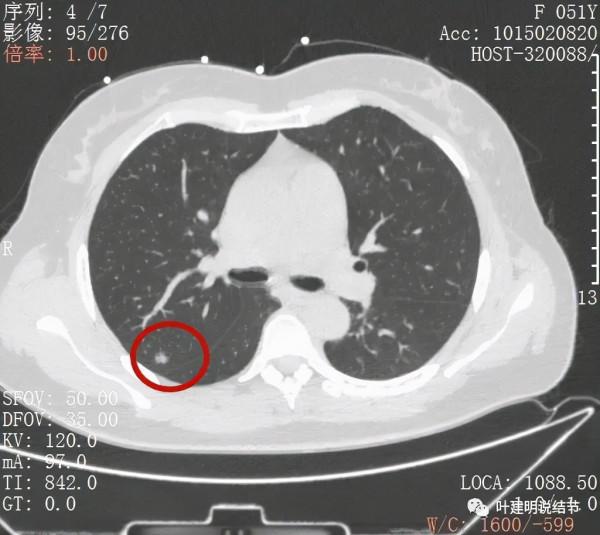

綜上所述,病軒A風險程度高,基本上應該是浸潤性腺癌,因為這麼小,是混合磨玻璃,且實性成分佔比較高,所以可能是至少腺泡型為主(也可能含更高風險亞型)伴貼壁成分(因為有磨玻璃成分,雖佔比少);B病灶考慮不典型增生可能性大,不能排除原位腺癌,若沒有A在,它可安全隨訪;C病灶考慮至少原位腺癌,也可能是微浸潤性腺癌,因為密度較高。若病為A在,它也因為過小,可隨訪。好在三個病灶都在上葉後段,那麼如果做上葉後段切除能一次解決目前所有病灶。所以我是建議其儘早手術的。今天要分享這個病例的目的還不是在這,而是我們再來看她2年前的片子,看病灶情況的演變,帶給我們的思考。先看其2年前的片子:

上圖示病灶A,當時很淡,三角形,邊緣模糊,其實更像區域性炎性病灶。

上圖是病灶B,與今年的相比沒什麼大的變化,直徑與密度輪廓均相似,說明病灶較為穩定,相對惰性

上圖是C病灶,也是微小結節,也沒有明顯變化。

當時是市區另外醫院做的CT,那時候的影像報告只提到右上葉約5毫米的磨玻璃結節,描述上沒有提到另外兩個病灶,我懷疑當時只關注到的是B病灶。患者住進來後,經過術前準備我們為其進行了“單孔胸腔鏡下右上葉後段切除加淋巴結采樣術”。下面是術後病理報告: